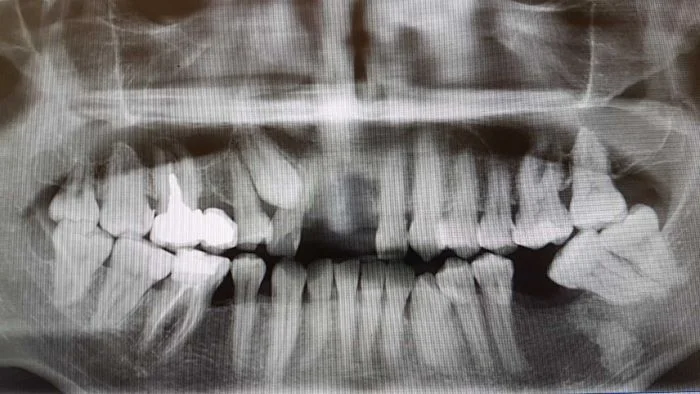

Read MoreИнтересный и сложный случай. Пациенту 36 лет. Наверху слева (или справа если от пациента) можно увидеть непрорезавшийся клык. Внизу слева - новообразование - остеома…